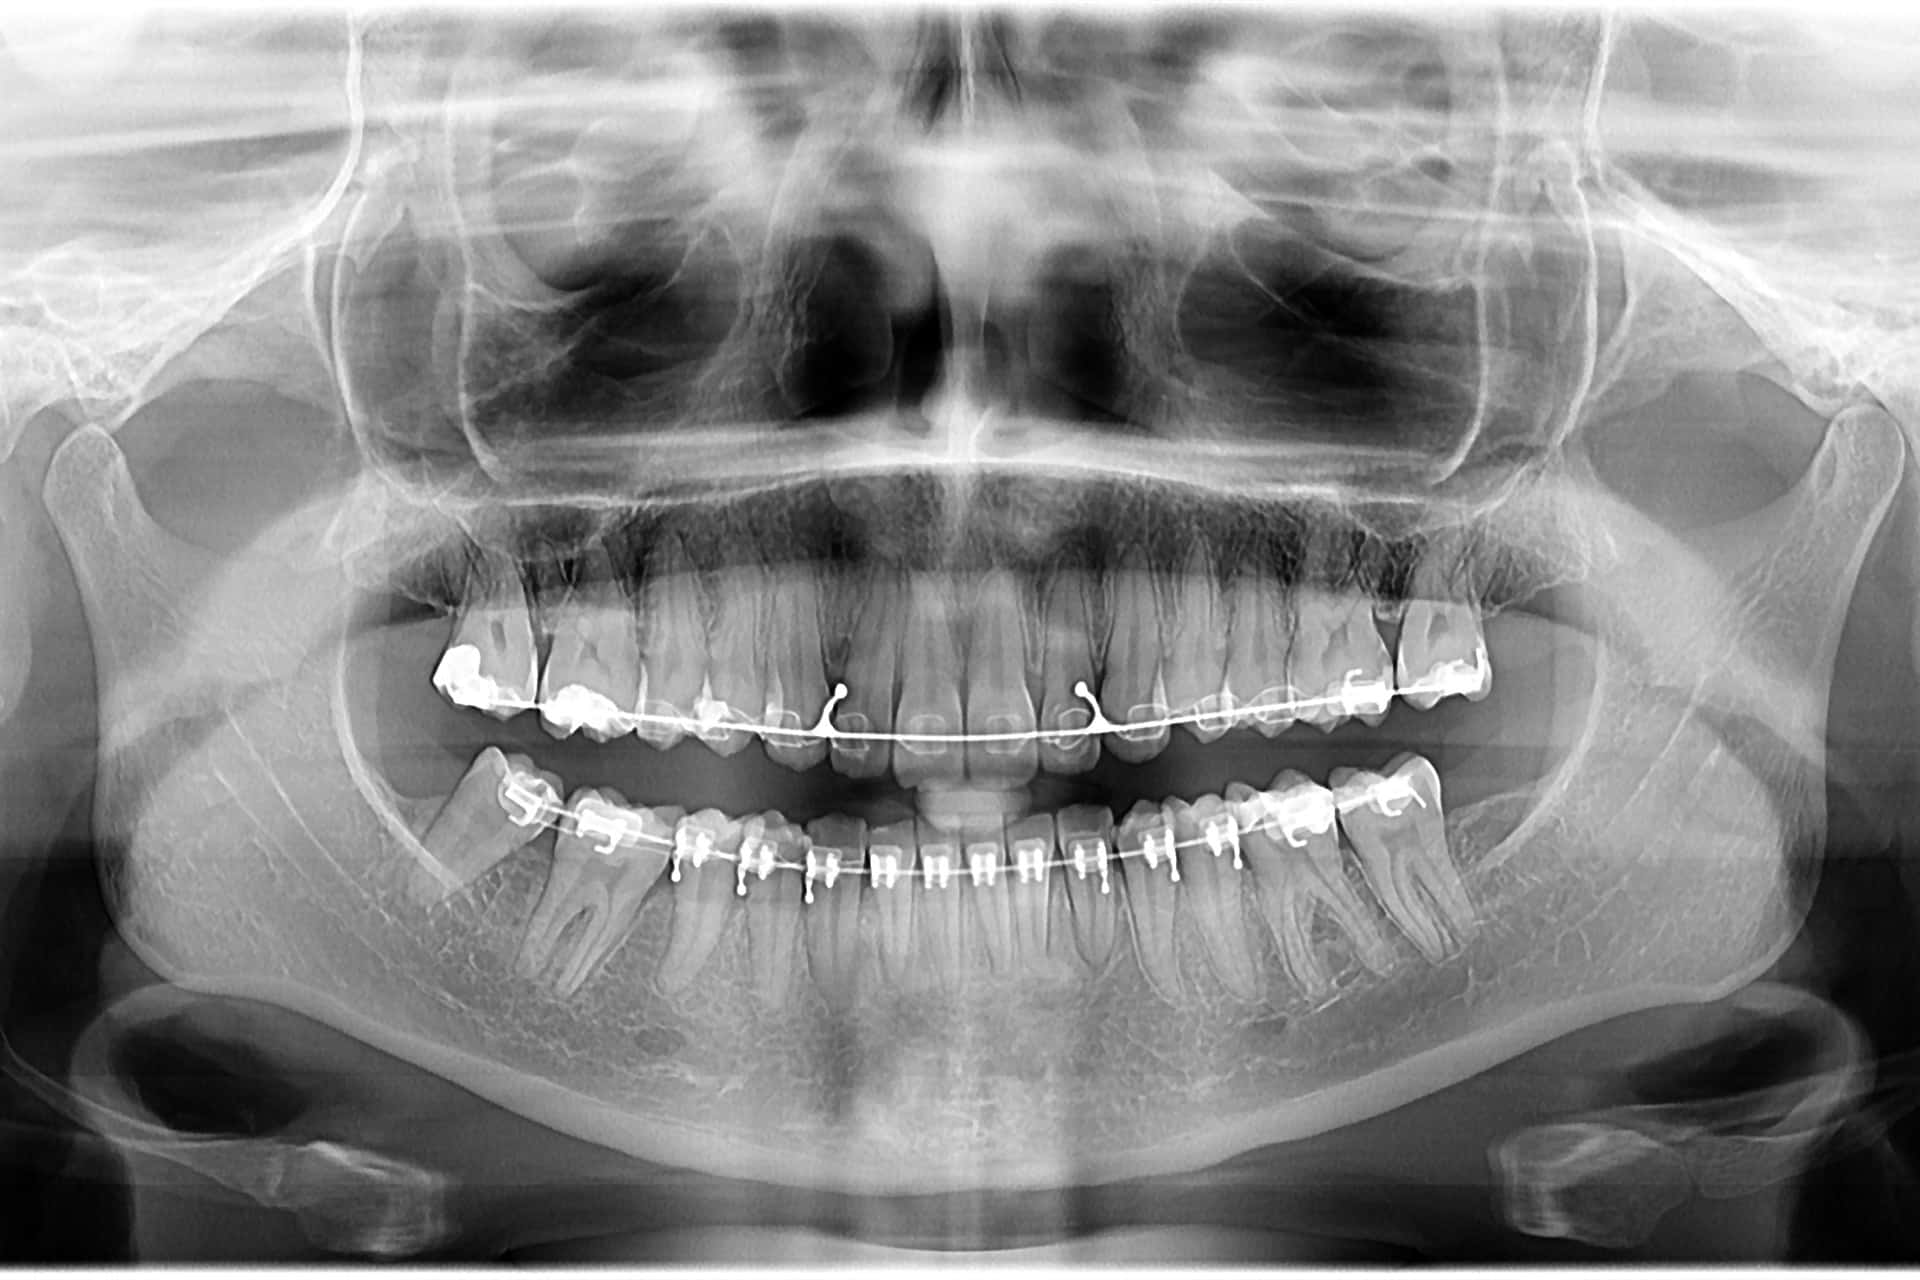

La ortodoncia es la especialidad de la odontología que se encarga de corregir las malposiciones de los dientes y las alteraciones de la mordida. Si tienes los dientes torcidos, apiñados o una mordida abierta o cruzada, la ortodoncia puede ayudarte a lograr una sonrisa más estética y funcional.

Son los aparatos más tradicionales. Pueden ser metálicos, de cerámica o zafiro, y se adhieren a los dientes para aplicar fuerza y moverlos gradualmente.

Equipos de radiología dental y Software de imagen para planificación y diagnóstico.